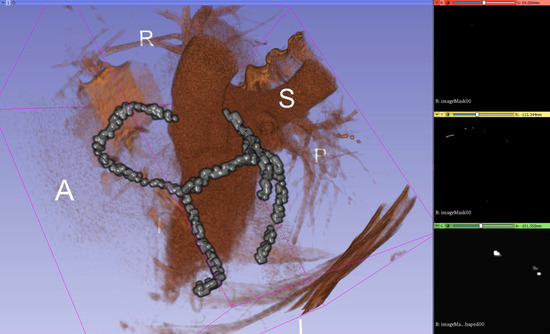

Visual validation for the output volumes is provided, as shown in Figure 6. The ground truth centerline is depicted in red. The segmentation (after thinning) is seen in green, making it easier to check that the segmentation follows the centerline. Visual validation for other training configurations can be found in Figure A3.

Figure 6.

Patch size 256 × 256 × 128; a 3D Slicer rendering of ground truth (red) and centerline segmentation (green).

Figure A3.

Visual validation for different parameter configurations. The ground truth centerline is depicted in red. The segmentation (after thinning) is seen in green for (a) 128 × 128 × 96, batch size 1, reduction 1, only patches with ground truth; (b) 128 × 128 × 128, batch size 2, reduction 2, only patches with ground truth; (c) 256 × 256 × 128, batch size 1, reduction 2; (d) 320 × 320 × 64, batch size 1, reduction 4; and (e) 384 × 384 × 48, batch size 1, reduction 4.